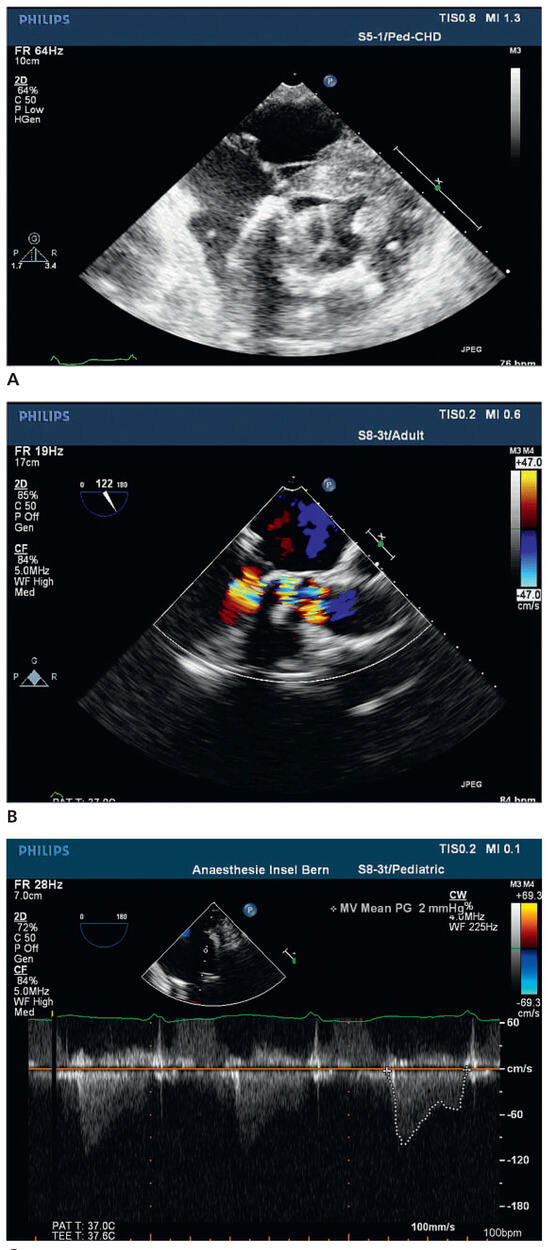

Worldwide First Surgical Implantation of a Transcatheter Valved Stent in Mitral Position

Case report